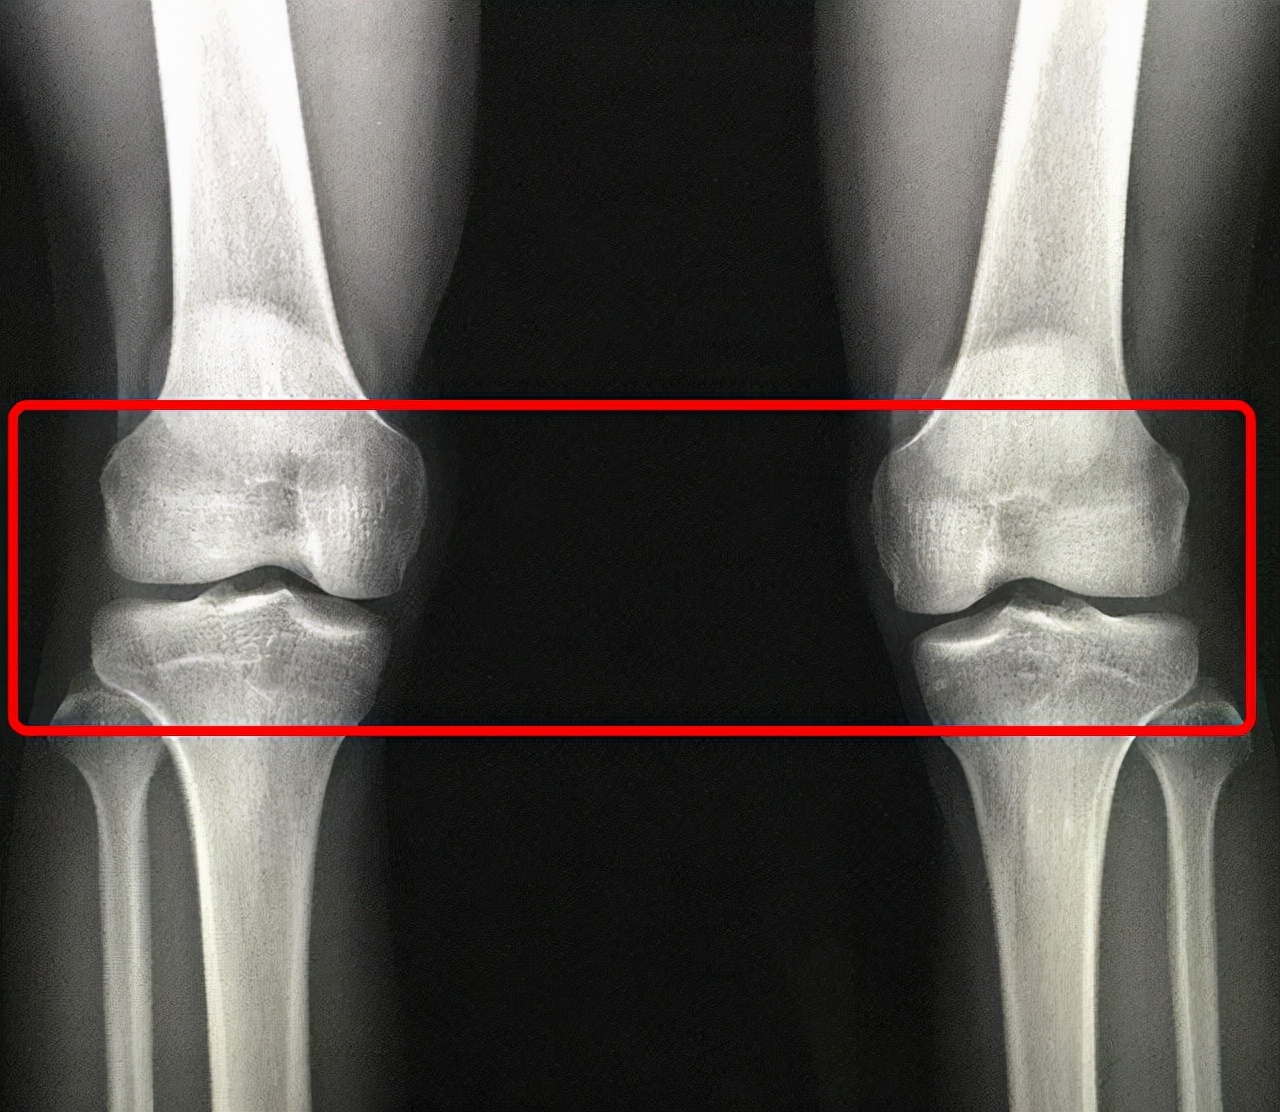

骨骺線在外觀是看不到的,一般來說都是要透過照片,最普通的就是x光照片。

x光照片可以看到兩端的骨,但是骨骼是板狀的,一個透明的軟骨,所以照片是看不到。因為它沒有足夠的密度,所以X光是看不到的。

所以我們看骨骼是板還是線,要透過X光照片來看。